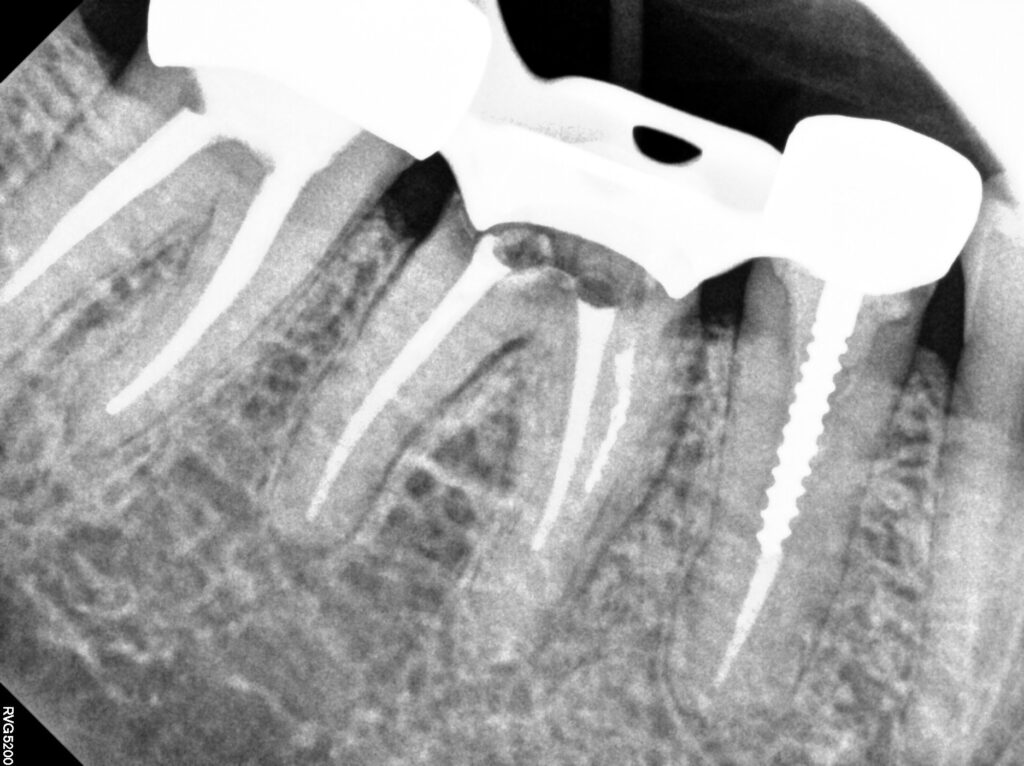

중요한 코어단계인데요

크라운을 유지해줄만한 버팀목이 없기 때문에

포스트를 이용한 레진코어를 만들었어요